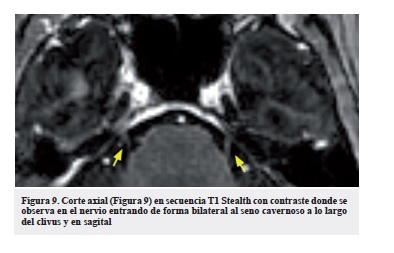

Cuando existe una lesión tumoral en la topografía de un nervio craneal, la tomografía puede ser útil para la detección de compromiso óseo, sin embargo, el reconocimiento de los nervios de pequeño tamaño como el abducens son de difícil caracterización, pues la presencia del líquido cefalorraquídeo cistenal hipodenso no proporciona un adecuado contraste con estas estructuras (Figura 7). La administración de contraste intratecal para realización de cisternografía nos puede brindar un mejor contraste y visualización (Figura 8), sin embargo, hoy en día considerado un procedimiento invasivo que no aporta información adicional en comparación a la resonancia, que ofrece mejor contraste en la caracterización de los nervios, debido a la disparidad que nos proporciona el líquido cefalorraquídeo adyacente en secuencias ponderadas en T2 (nervio isointenso rodeado de líquido hiperintenso). La RM (Figura 9 y 10) es el método de elección para evaluar los nervios craneanos, y el VI no es la excepción. Estos nervios constituyen un grupo de estructuras que han adquirido durante su desarrollo filogenético un alto grado de especialización. Hay 12 pares de nervios a los cuales nos referimos por su nombre o número correspondiente y son visibles a través de técnicas de resonancia. En la evaluación convencional del cerebro con RM pueden ser observados los nervios más grandes como el óptico, oculomotor, trigémino, facial y vestibular; sin embargo, para los otros nervios, es necesario realizar cortes finos y reconstrucciones multiplanares, así como secuencias adicionales como Fast Imaging Employing Steady State Adquisition (FIESTA) (Figura 11), Short Tau Inversion Recovery (STIR), Fluid Attenuated Inversion Recovery (FLAIR) o Cube., estas dos últimas, utilizadas sobretodo en la caracterización y extensión de algunos tumores.

Teniendo en cuenta la localización anatómica del nervio abducens en su recorrido a través de la cisterna pontina, es posible identificarlo a través de las distintas secuencias de resonancia magnética, en especial, utilizando las secuencias T1 con gadolinio, T2 y FIESTA, preferiblemente con cortes milimétricos y en 3D de 1 mm de espesor, ya que permite reconocerlo en los planos ortogonales radiológicos convencionales, y de esta forma reconocer sus relaciones anatómicas.